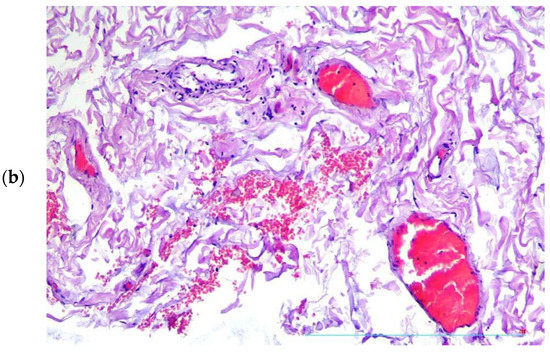

Condition “Vasa Vasorum” in Patients with Thoracic Aortic Aneurysm

by Petr V. Chumachenko, Alexandra G. Ivanova, Mariam Bagheri Ekta, Andrey V. Omelchenko, Vasily N. Sukhorukov, Alexander M. Markin, Yuliya V. Markina and Anton Y. Postnov

J. Clin. Med. 2023, 12(10), 3578; https://doi.org/10.3390/jcm12103578 - 20 May 2023

It is known that vasa vasorum contributes substantially to the blood supply and nutrition of one-third of the wall of the ascending thoracic aorta. Therefore, we focused on studying the relationship between inflammatory cells and vasa vasorum vessels in patients with aortic aneurysm. [...] Read more.

It is known that vasa vasorum contributes substantially to the blood supply and nutrition of one-third of the wall of the ascending thoracic aorta. Therefore, we focused on studying the relationship between inflammatory cells and vasa vasorum vessels in patients with aortic aneurysm. The material for the study was biopsies of thoracic aortic aneurysms taken from patients during an aneurysmectomy (34 men, 14 women, aged 33 to 79 years). The biopsies belonged to patients with non-hereditary thoracic aortic aneurysm. An immunohistochemical study was carried out using antibodies to antigens of T cells (CD3, CD4, CD8); macrophages (CD68); B cells (CD20); endothelium (CD31, CD34, von Willebrand factor (vWF)); and smooth muscle cells (alpha actin). Samples without inflammatory infiltrates contained less vasa vasorum in the tunica adventitia than samples with inflammatory infiltrates, and this difference was statistically significant p < 0.05. T cell infiltrates in the adventitia of aortic aneurysms were found in 28 of 48 patients. In the vessels of the vasa vasorum, surrounded by inflammatory infiltrates, T cells that adhered to the endothelium were found. The same cells were also localized in the subendothelial area. The number of adherent T cells in patients with inflammatory infiltrates in the aortic wall dominated the number of these cells in patients without inflammation of the aortic wall. This difference was statistically significant, p < 0.0006. Hypertrophy and sclerosis of the arteries of the vasa vasorum system, the narrowing of their lumen, and, as a result, impaired blood supply to the aortic wall, were found in 34 patients with hypertension. In 18 patients (both in patients with hypertension and in patients without hypertension), T cells that adhered to the vasa vasorum endothelium were found. In nine cases, massive infiltrates of T cells and macrophages were found, which surrounded and squeezed the vasa vasorum, preventing blood circulation. In six patients, parietal and obturating blood clots were found in the vasa vasorum vessels, which disrupted the normal blood supply to the aortic wall. We believe that this indicates the importance of the state of the vessels of the vasa vasorum in the development of an aortic aneurysm. In addition, pathological changes in these vessels may not always play a primary role, but always a very important role, in the pathogenesis of this disease. Full article